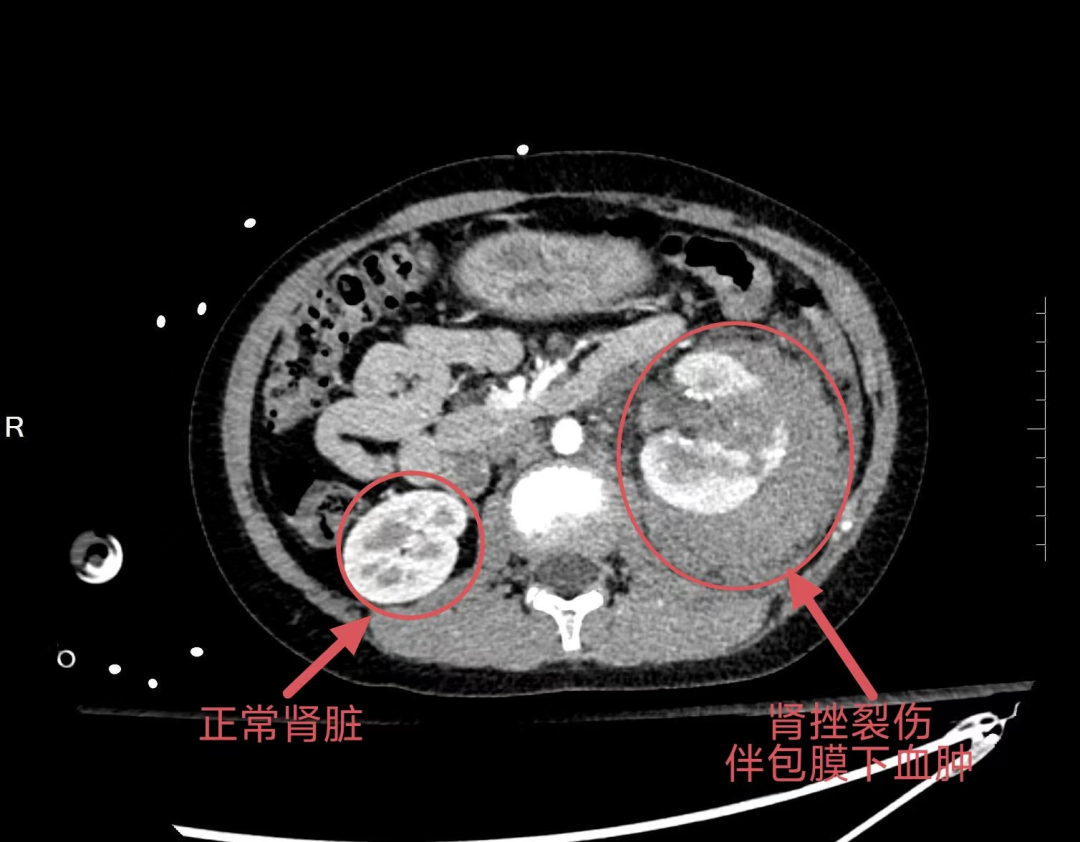

患者为一名10岁男童,因意外受伤导致左背部剧烈疼痛、血尿,被紧急送入我院。CT检查提示:左肾周巨大血肿,活动性出血明确。患儿面色苍白,血压持续下降,血红蛋白急剧降低,生命危在旦夕。